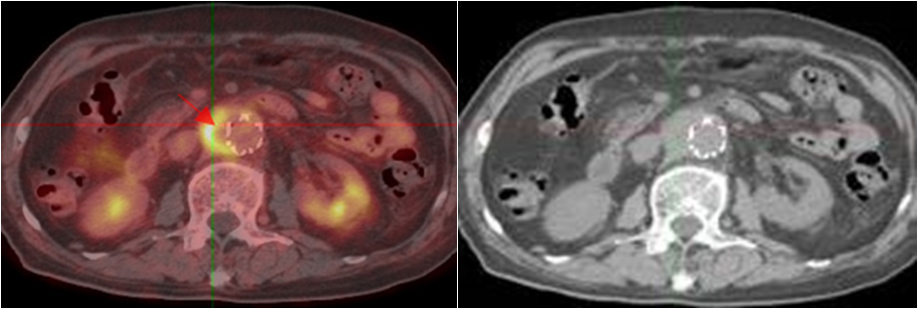

老年男性,反復發(fā)熱1年余;10年前因主動脈夾層行支架植入。PET/CT顯示支架周圍主動脈管壁增厚,代謝明顯增高,診斷為支架周圍感染。